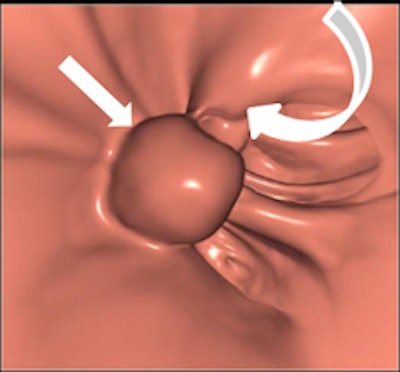

Left: Large pedunculated polyp in the sigmoid (white arrow). Right: Corresponding 3D image of this pedunculated polyp with a 2-cm head (white arrow). Images courtesy of Philippe Lefere, MD.Moreover, the procedure is patient-friendly and it can be performed on an outpatient basis. No sedation is necessary, the examination time is short, it can be performed the same day as the optical colonoscopy, it can detect important pathology outside of the colon, and patient preparation is possible without interruption of normal daily activities, Lefere said. The main drawbacks are that radiation is used, polypectomy is not possible, there is the potential for superfluous explorations (iatrogenic pathology), patient preparation is still needed, it involves a relatively steep learning curve, and long interpretation times during the initial phase.